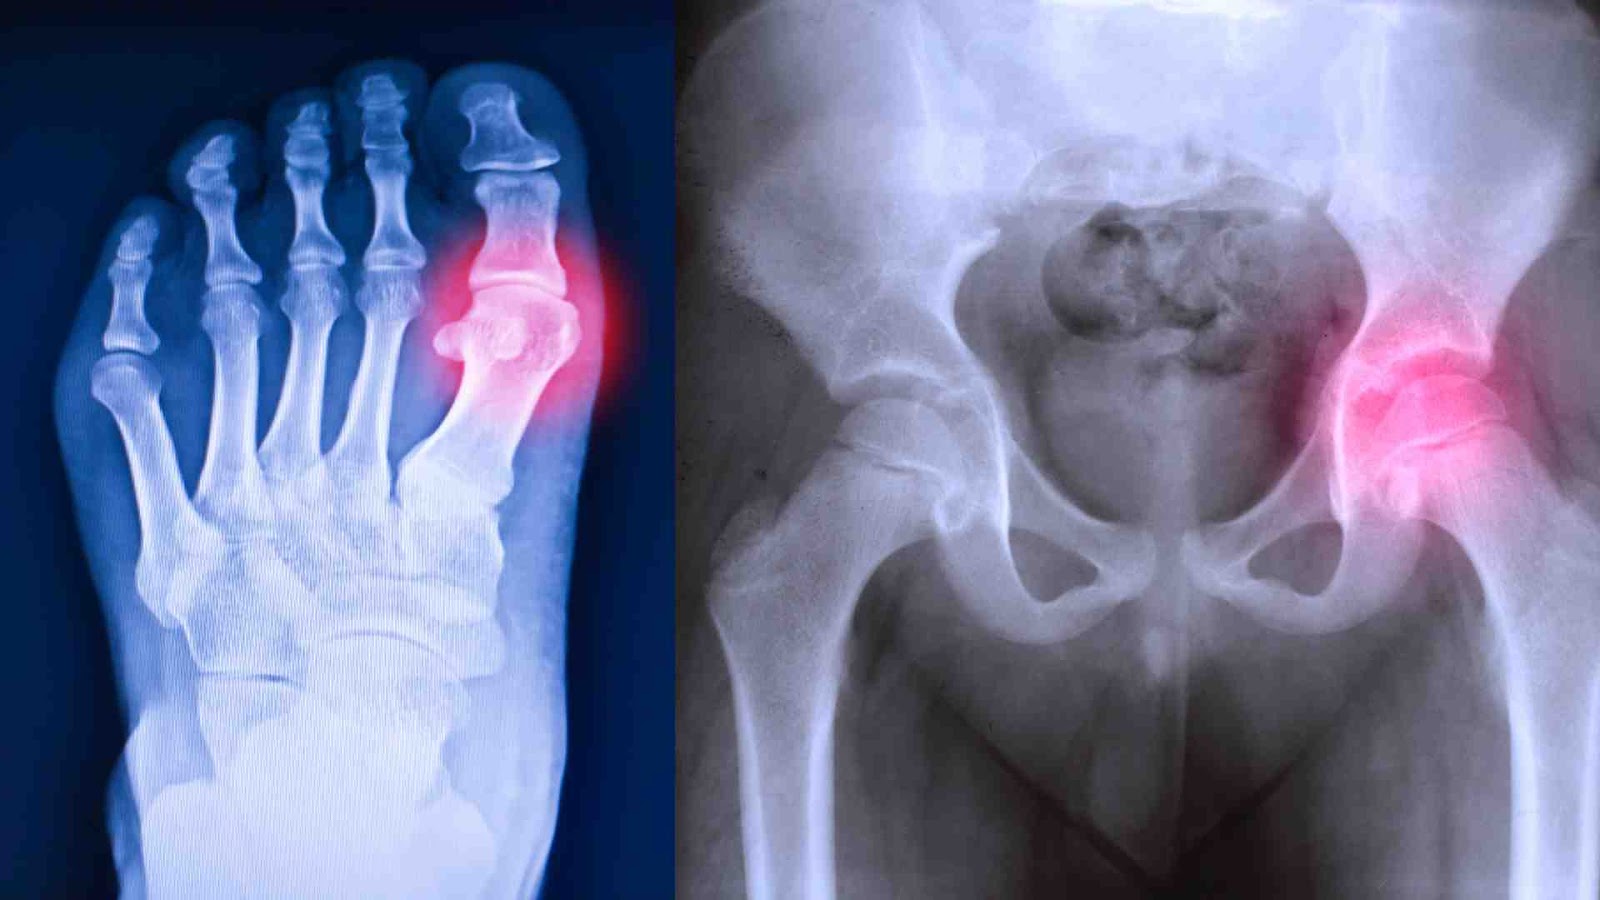

When it comes to arthritis, the latest science reveals that inflammation causes the pain, not wear and tear on the joints. Paula Goodyer explains the best way to tackle it.

Let’s reboot our thinking about osteoarthritis - it’s less about ‘wear and tear’ on our joints and cartilage and more about inflammation.

“We now know that a main driver of both osteoarthritis and pain is inflammation, and if we can tackle the processes that cause it, we can help prevent or reduce the impact of arthritis.”

If you’re feeling pain or stiffness in your hands, big toe, knees or hips or wondering why your joints make clicking noises, feel like they grate or have become inflexible, then it’s worth a trip to the doctor..